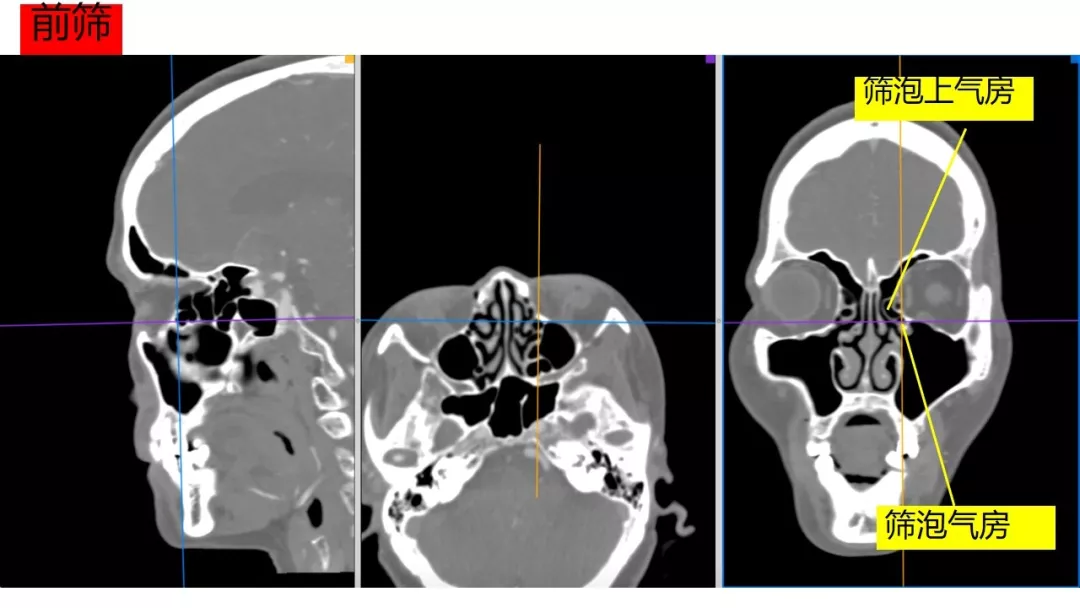

Osirix冠矢轴